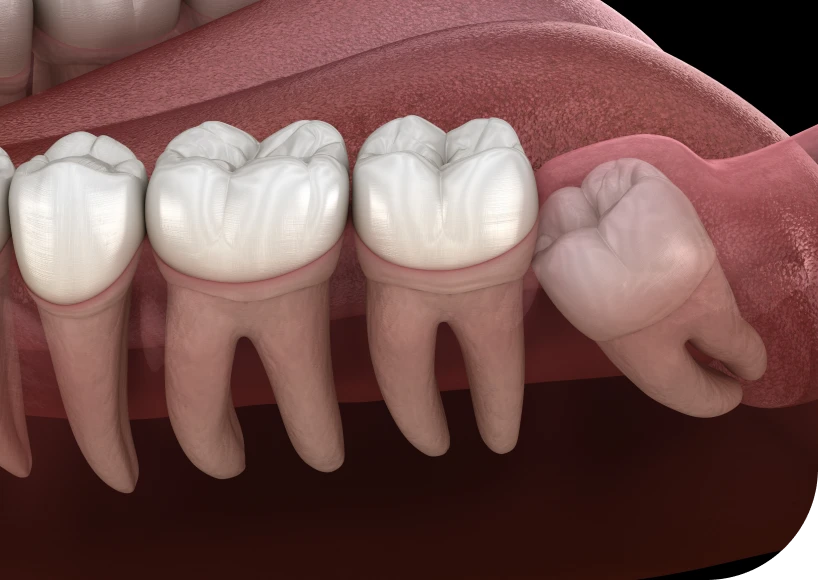

Les dents de sagesse, appelées également troisièmes molaires, apparaissent généralement entre 17 et 25 ans. Elles se trouvent tout au fond de la bouche, en haut et en bas. Toutefois, elles posent souvent problème, car elles manquent de place pour sortir correctement. Ainsi, leur extraction devient parfois indispensable. Cette chirurgie orale courante se pratique sous anesthésie locale ou générale, selon les cas.

Tout d’abord, les mâchoires modernes sont souvent trop étroites. Par conséquent, les dents de sagesse poussent de travers ou restent incluses. Dans ces cas, elles peuvent provoquer des douleurs, des inflammations et des troubles de l’alignement dentaire.

Par ailleurs, une dent de sagesse peut pousser contre la molaire voisine. Cela entraîne des douleurs, un déplacement dentaire ou une résorption de racines. Dans ce contexte, l’extraction évite des complications à long terme.